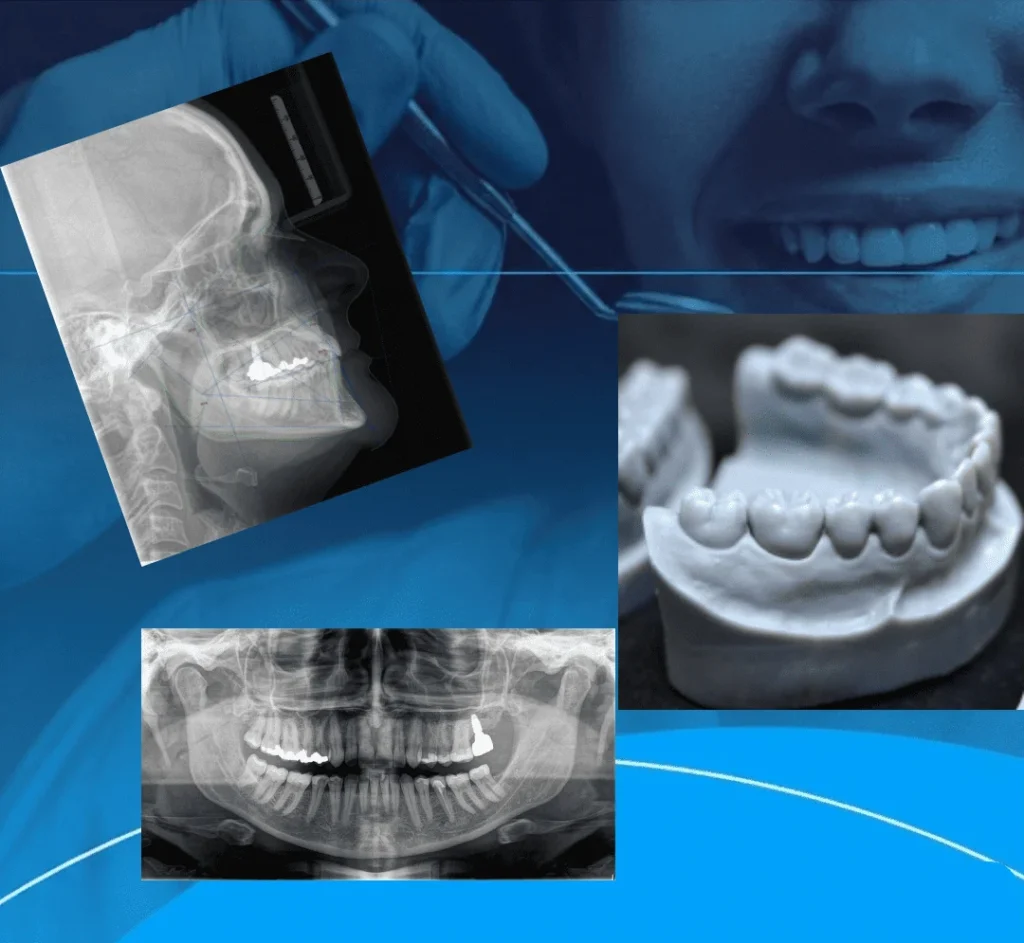

Conjunto de exames, de acordo com a necessidade do dentista:

Panorâmica, Telerradiografia lateral, traçados cefalométricos, telerradiografia frontal, raio-x carpal, radiografias periapicais dos dentes, fotografias e modelos ortodônticos.

Fotografias odontológicas são registros detalhados da boca e face do paciente, usando técnicas e equipamentos específicos para diagnóstico, planejamento, acompanhamento de tratamentos (como o antes e depois), comunicação com laboratórios e marketing, dividindo-se em: fotos extraorais (rosto) e intraorais (dentro da boca), essenciais para documentar a estética e saúde bucal com precisão

Os modelos ortodônticos são cópias fiéis das estruturas presentes na boca. Podem ser obtidos de duas formas: através de uma moldagem ou do escaneamento intraoral digital.

São usados para estudo, com fins de planejamento do tratamento ortodôntico ou para trabalho, sobre os quais os profissionais podem confeccionar aparelhos e próteses.